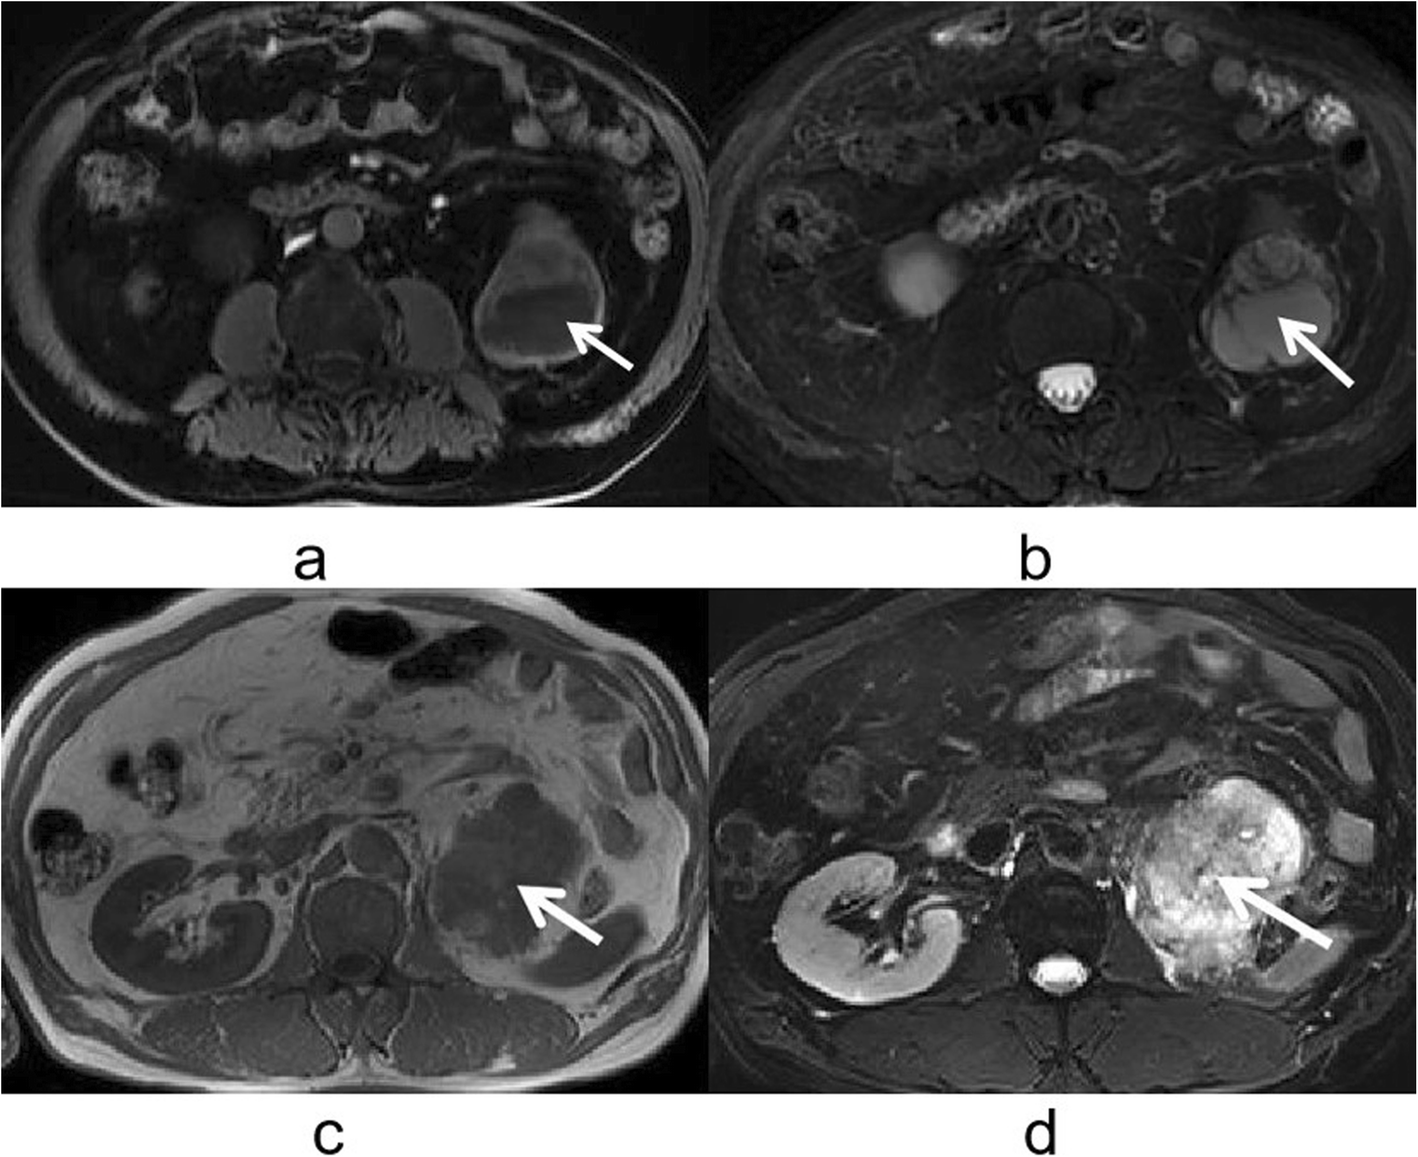

Fig. 5

a-d. CRCC and CCDC of MR imaging. a CRCC appeared hypointense on T1-weighted images. b CRCC appeared hyperintense on T2-weighted images. c CCDC appeared hypointense on T1-weighted images. d CCDC appeared hypointense on T2-weighted images